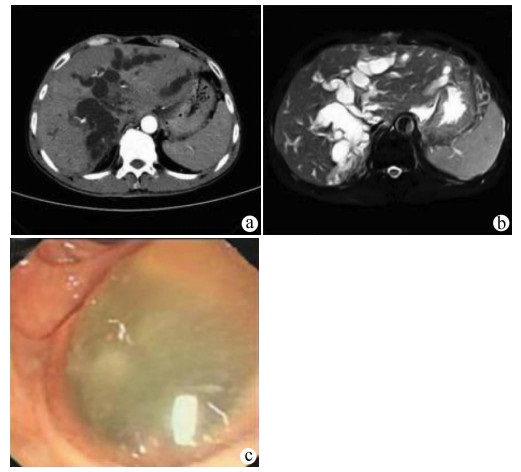

Recurrence after hepatectomy for primary gastrointestinal stromal tumor of the liver: A case report

Kangwei LIU, Xin GENG, Lei WANG, Cijun PENG

2021, 37(12): 2893-2895. DOI: 10.3969/j.issn.1001-5256.2021.12.031

Abstract(939) HTML (236) PDF (2357KB)(47)

Abstract: